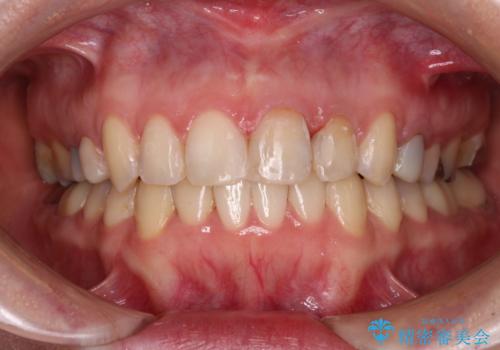

【モニター】前歯のデコボコと奥歯の虫歯 インビザライン治療と奥歯のセラミック治療

- 前歯のデコボコと奥歯の虫歯を気にして来院された患者様です。

主に下顎歯列全体の後方移動とIPR(歯と歯の間を削る)によってデコボコが解消するように設計し、インビザラインにより治療を行うこととしました。

矯正治療後半に下顎左右奥歯をセラミッククラウンにて補綴し、その後インビザラインによる歯列の仕上げを行うこととしました。

下顎前歯の叢生が速やかに改善されたため、1年3か月で治療を終えることができました。

下顎前歯は後戻りを起こしやすいため、舌側を細いワイヤーで固定することで後戻り対策を行っています。